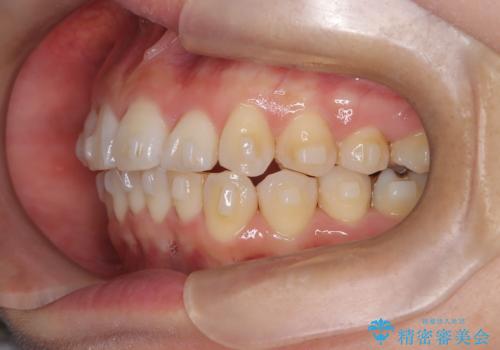

- 「歯のガタつきが気になる」「前歯の真ん中がずれている」との主訴で来院されました。診察の結果、上下の歯列に中等度の叢生(凸凹)があり、特に前歯の位置のずれ(正中の偏位)が目立つ状態でした。見た目だけでなく、かみ合わせにも影響を与える可能性があるため、全体的なバランスの改善が必要と診断しました。

治療はインビザラインを使用し、1~2週間ごとに新しいマウスピースに交換しながら段階的に歯を移動させていきました。特に上下の正中が揃うよう、奥歯や前歯の位置関係に注意を払いながら細かく設計を調整。途中の確認でも、左右のバランスが取れてきたことをご本人も実感されていました。

治療期間は約1年半で、ガタついていた歯列はきれいに整い、上下の前歯の真ん中もぴったりと揃えることができました。透明なマウスピースのため周囲に気づかれず治療が進み、快適に続けられたとの感想もいただいています。